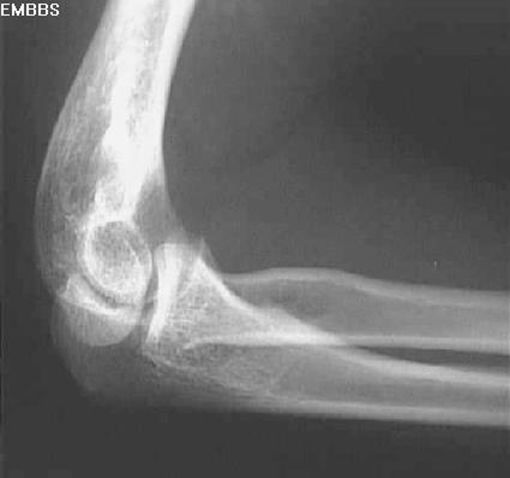

肘关节脱位

肱骨髁上骨折